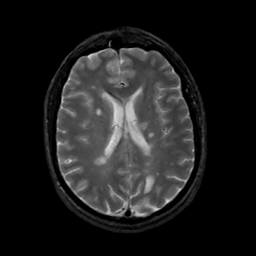

MR Study #12, May 12, 1991 -- Slice #30